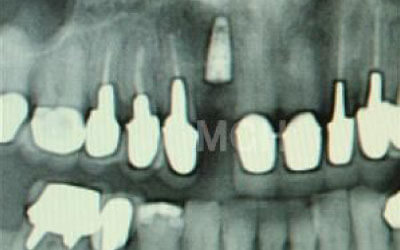

Dr.大野

歯が抜けた後の治療について、多くの方が悩まれています。

特に、抜けたのが前歯ですとなおさら気になりますよね。

今回のご質問ですが、抜けた部分の骨が薄いなどの理由で「インプラントはできない」と言われた可能性があります。

前歯はもともと骨が薄く、歯が抜けると時間の経過とともにさらに骨が痩せてきてしまうので、インプラント治療の難易度が高い場所です。

ただ結論からお話すると、インプラント治療は可能です。

なぜなら、もし仮に骨が薄くても、骨の治療によって厚みが増せば、安全にインプラント治療が行えるからです。

なお、前歯のインプラント治療をご希望の方には、注意していただきたい点が4つほどあります。

1)インプラント治療を行う前に、骨の治療が必要かもしれません。

2)骨の治療から始めると、その分、治療期間が長くなります。

3)骨の治療は、通常のインプラント治療よりも難易度が高いため、経験の豊富な先生やインプラント認定医のいる歯科医院で治療を受けることをお勧めします。

4)骨の状況をしっかり把握するためにも、CT撮影が必須となります。

また、インプラント治療においては、周囲の歯の状況や咬み合わせの問題などもしっかりと考えて治療するのがとても大切です。

そのため、残っている歯についてもきちんと診査してくれるクリニックが良いでしょう。